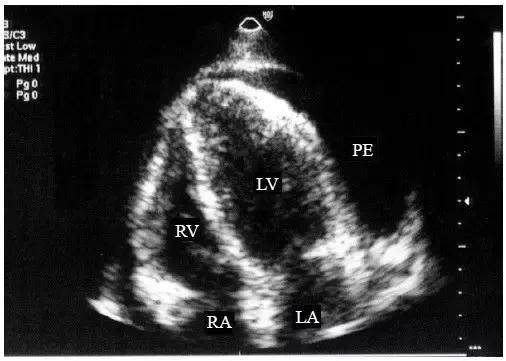

【少量心包积液】

液体仅潴留在左心室后壁和侧壁心包腔内,内径<10mm(图1)。

图1 少量心包积液的二维超声心动图表现

左心室后壁心包腔内少量液性暗区,内径< 10mm